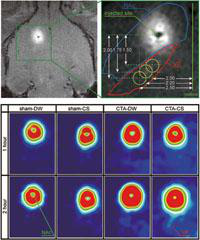

人間や動物の行動がどのような脳の働きに基づいて生じるのかを解明することを、研究目的としている。そのために、個体の維持にかかわる食行動や種族の保存を目的とした生殖行動など、もっとも基本的な動機づけ行動の神経機構について、多彩な方法論を駆使して実験的研究を進めている。とくに、食行動の発現には味覚が重要な役割を果たしているので、脳内の味覚情報処理機構を中心に検討を行っている。神経生理学的研究としては、自由行動中あるいは麻酔下のラットから神経細胞の活動電位を記録し、感覚入力から運動出力に至る動的な情報処理様式を解析している。免疫組織化学的研究においては、食行動の発現にかかわる 脳部位を特定し、関連情報の流れを空間的にマッピングしている。行動学的研究においては、脳の局所的な機能剥奪や薬物投与が味覚関連行動に及ぼす効果を検 討している。さらに、食行動や味覚情報処理にどのような脳内物質が関与するのかを明らかにするため、神経生化学的・分子生物学的研究も進めている。このような基本的行動にかかわる神経機構の解明を糸口として、認知、情動体験、学習、記憶などのより高次な脳機能の理解を目指している。